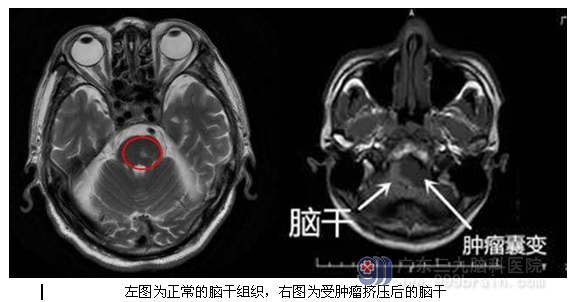

李某某,男,31岁,左侧面部麻木、耳鸣、听力下降2月,门诊CT显示颅内占位病变,遂安排入院治疗。入院后完善相关术前检查,磁共振显示左侧桥小脑角区5.2CM*2.8CM*5.6CM囊实性异常信号影,囊变的肿瘤已经将脑干压得很薄,手术中轻微牵拉囊壁就会导致心跳减慢或停止,为保证病人的安全性以及手术成功,科室组织专家反复对手术的过程进行研讨,最后决定择期行全麻下左侧桥小脑角占位性病变切除术,手术由广东三九脑科医院神经外一科主任张良主刀完成,术中见肿瘤包膜完整,分为囊实性两部分,术后过程顺利,术后患者恢复良好,未见并发症,术后MR提示肿瘤切除。

↑手术前后对比

广东三九脑科医院神经外一科主任张良医师介绍:三叉神经鞘瘤为起源于三叉神经根、半月节或三周围支的脑外良性肿瘤,占颅内原发肿瘤的 0.2%。 影像学检查,特别是MRI无颅骨伪影和 具有多维成像特点,除清晰显示肿瘤本身特征外,还能了解病变范围及与周围组织的关系,是三叉神经鞘瘤诊断、鉴别诊断和辅助手术治疗的重要检查方法。本例患者MR清楚显示肿瘤的大小,形态等。尤其下极肿瘤囊变压迫脑干,脑干变得很薄,术中轻微牵拉肿瘤导致心率下降,甚至心跳停止,手术中心跳停止6秒,多次心跳低于40次/分,然后会恢复。